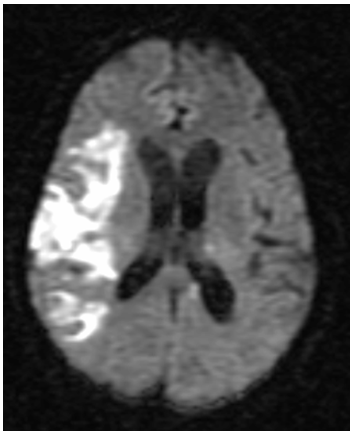

Furthermore, a chest CT scan was performed, showing a lung lesion in the low left lobe including left bronchus, lung lymphadenopathy, left pleura metastatis, left kidney stroke and bilateral suprarenal metastasis. A brain MRI confirmed right middle cerebral artery stroke, left posterior- inferior cerebellar artery stroke and right anterior cerebral artery stroke (Figure 3).

Figure 3Brain MRI, difussion-weighted images showing right middle cerebral artery stroke.